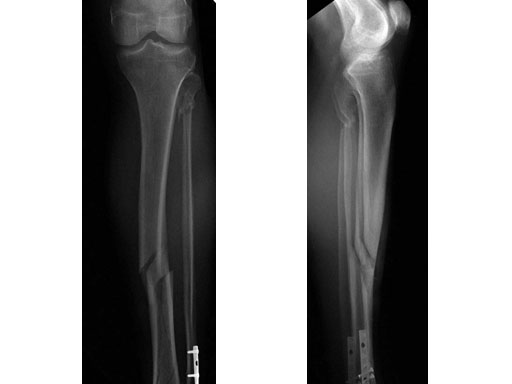

48-year-old male. Tibia shaft fracture with fibula fracture.

Case provided by Hermann Bail, Berlin, DE